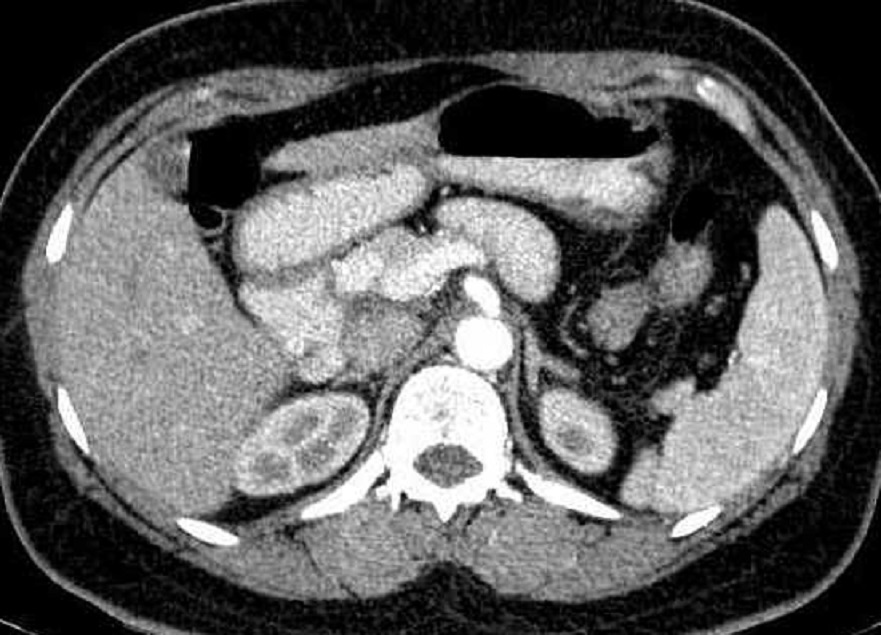

Meme cas en coupe TDM axiale plus contrast

intraveineuse Le tumeur devient hyperdense

apres injectionc . Image radiologique TDM

plus

contrast intraveineuse temps arterielle |